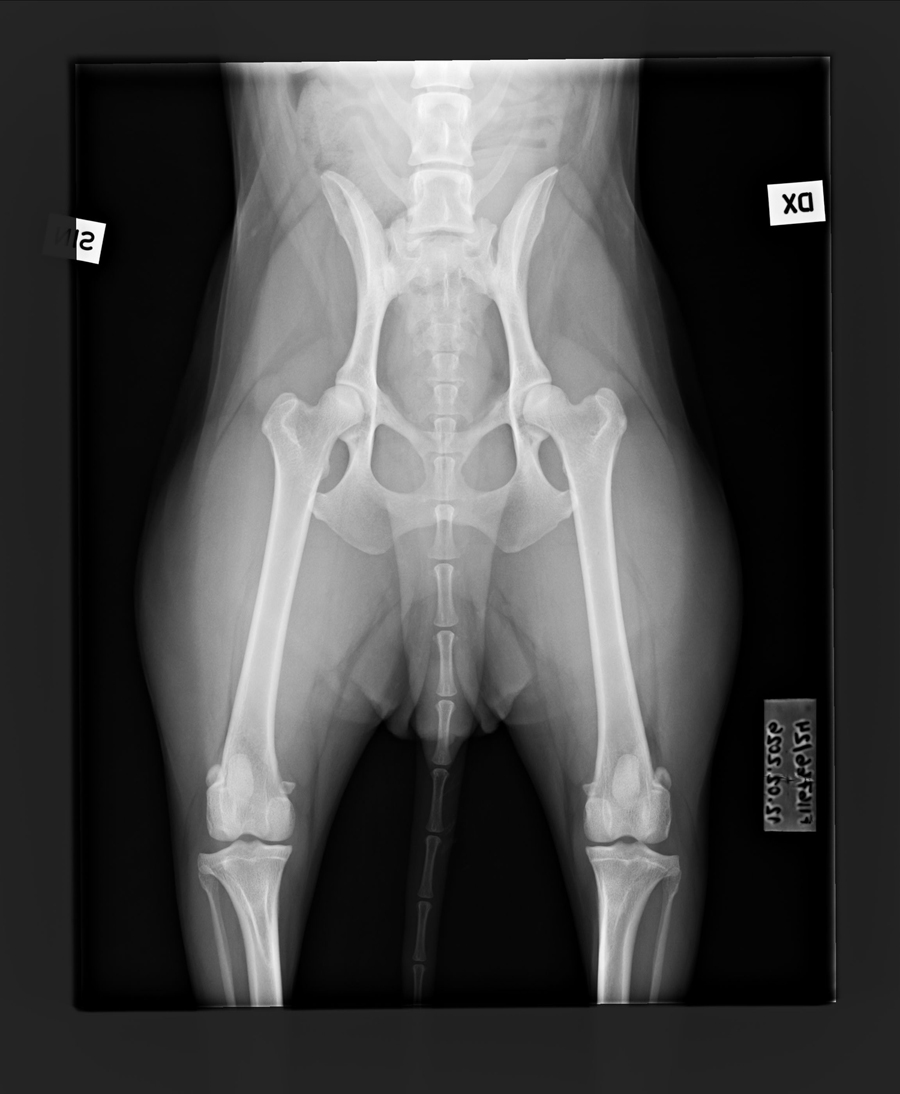

C/B |

1/0 (see Notes) |

- Finnish Kennel Club's elbow x-ray report Dec '25: Signs suggestive of medial coronoid disease; further information about the condition of the joints can be obtained, if necessary, by computed tomography (CT) examination

- Finnish Kennel Club's elbow CT report Feb '26: A small amount of new bone formation around the medial coronoid process of the left elbow